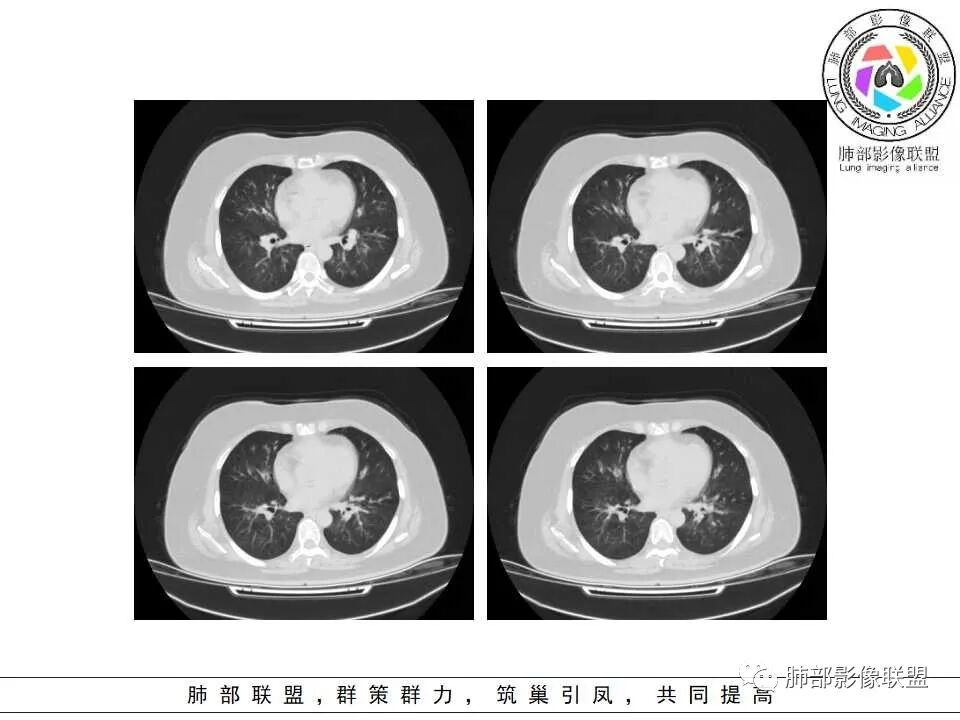

老年女性,发现白细胞升高两年,此次入院多次查外周血白细胞>30*10^9/L,淋巴降低,CRP显著升高,但病程中无发热,以细菌性炎不好解释;CT提示有脾大,结合外周血象,首先考虑存在血液系统疾病(白血病)基础,且未系统诊治;肺部CT提示双肺中轴间质增粗,伴随支气管管壁增厚?多发树丫及腺泡结节,部分呈点晕征,可见肺动脉分枝增粗,一元论考虑白血病肺部浸润;二院论考虑白血病并发气道侵袭曲霉。以患者病程进展看,更倾向于白血病肺部浸润。

肺动脉增粗,支气管有改变

左侧腔内有粘液栓,右侧支气管局部有扩张

肺动脉高压:性质待查,血象哪位老师解释一下,看右上支气管,怀疑以前都有过

1.多见于血液恶性肿瘤及造血干细胞移植患者。两肺多发,多见磨玻璃晕,有时病灶基底贴近胸壁形成楔形影。

2.很少支气管壁增厚,也无支气管扩张,少见树芽征。